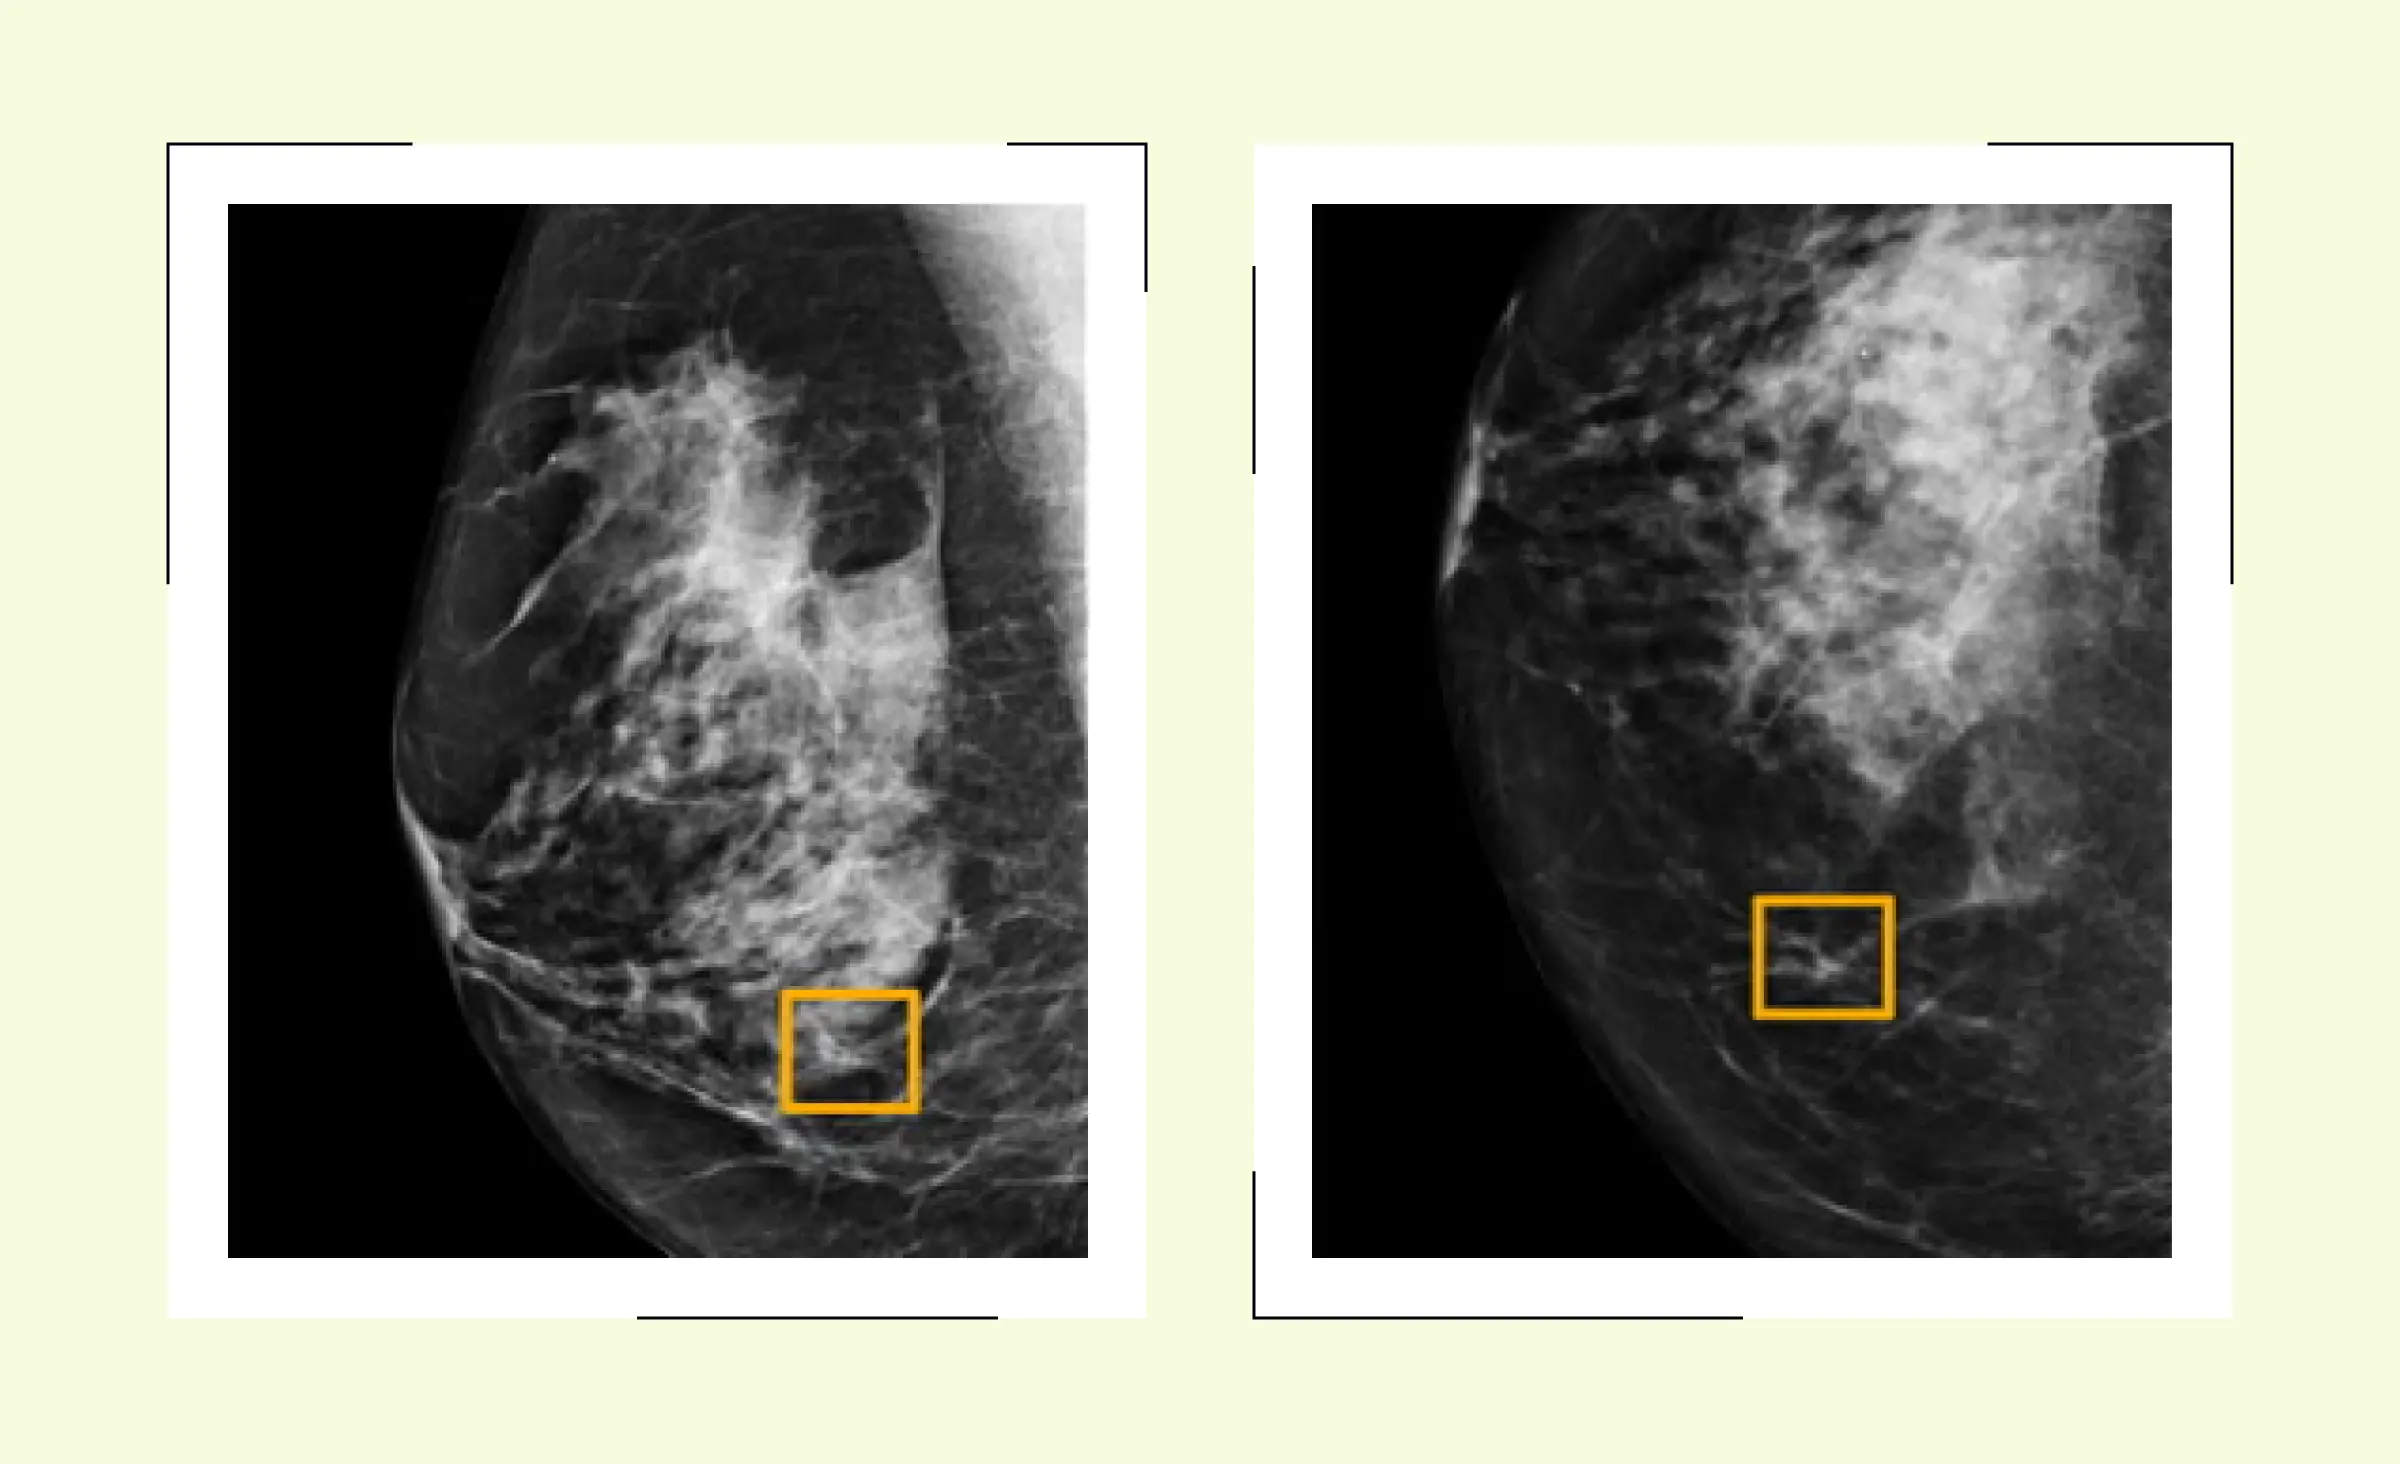

Many healthcare providers now rely on AI technology to examine and analyze medical images such as X-rays, MRIs, and CT scans. By using an AI tool, doctors can catch early signs of illness before symptoms appear. For example, AI-driven diagnostics help with disease detection for cancer, heart problems, and infections. IBM Watson is an example of an AI platform used in hospitals to assist with complex diagnostics and recommend next steps for patient care.

- Diagnostic accuracy: AI diagnostics can read a medical image and help find even small changes that might signal a problem. This improves diagnostic accuracy and diagnostic precision, so doctors give faster, more reliable results.

- Medical data: AI systems connect information from many sources, using patient data and medical data together with images, lab results, and clinical notes to make more accurate decisions. Healthcare diagnostics supported by AI help medical professionals spot patterns they could easily miss.